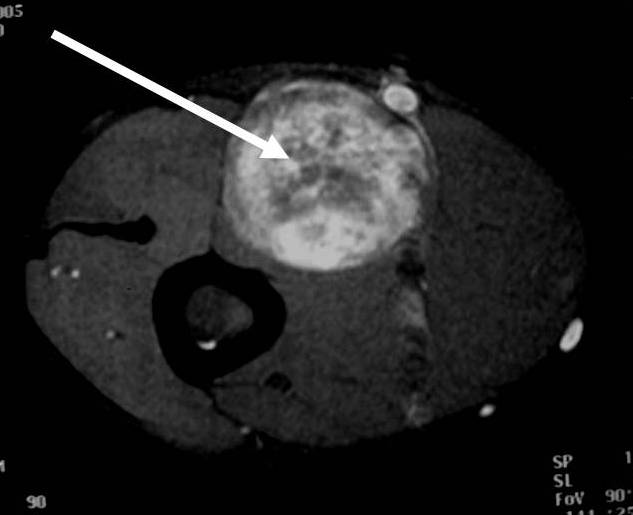

MRI appearance (Fig. 1 – 4)

• T2: High signal (myxoid areas) with some heterogeneity (Fig. 3)

o Target Sign: Low signal central area (cellular/collagenous area; Antoni A) and high signal peripheral area (myxoid area; Antoni B)

Fig. 1-4 MR image demonstrates a 5 cm intermuscular mass in the anterior compartment of the arm arising along the course of the neurovascular structures. Isointense to muscle on T1W image and heterogeneous high signal on T2W with low signal in the central area (Antoni A) and peripheral high signal (Antoni B), known as “Target Sign”. Coronal image shows a structure entering and exiting the mass (median nerve).